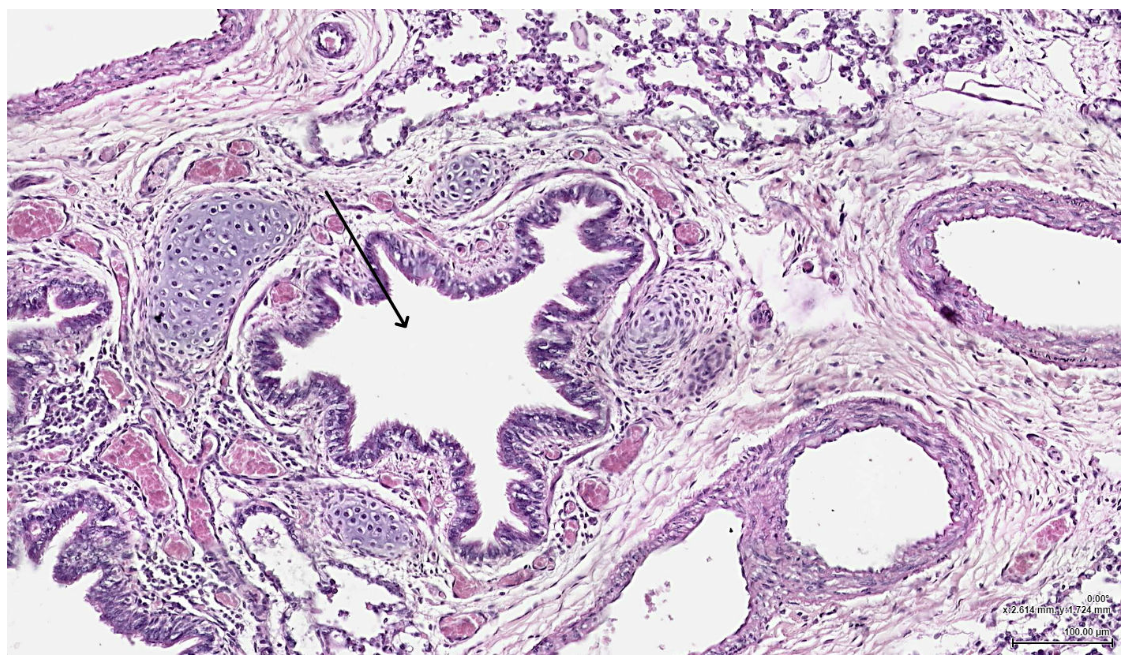

The structure indicated by the arrow most likely contains which of the following:

Elastic fibers

Which of the following cells would be LEAST likely to be found lining the indicated structure?

Clara cell

Right before passing through the indicated structure, where would air most likely travel?

Primary bronchus

The structure indicated by the arrow is most likely which of the following?

Alveolar Sac

The structure indicated by the arrow is most likely composed of which of the following?

Simple squamous epithelium

After passing through the indicated structure, where would air most likely travel next?